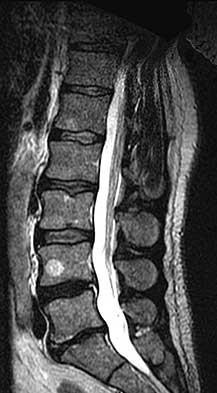

Question 13:

A 65-year-old male presents with neurogenic claudication. He reports pain radiating down both legs when walking, which is relieved by leaning forward on a shopping cart. MRI shows severe spinal stenosis at L4-L5. Which ligament thickens and contributes significantly to the dorsal compression of the thecal sac in this condition?

Correct Answer: Ligamentum flavum

Explanation:

In degenerative lumbar spinal stenosis, hypertrophy and buckling of the ligamentum flavum commonly cause dorsal compression of the thecal sac.